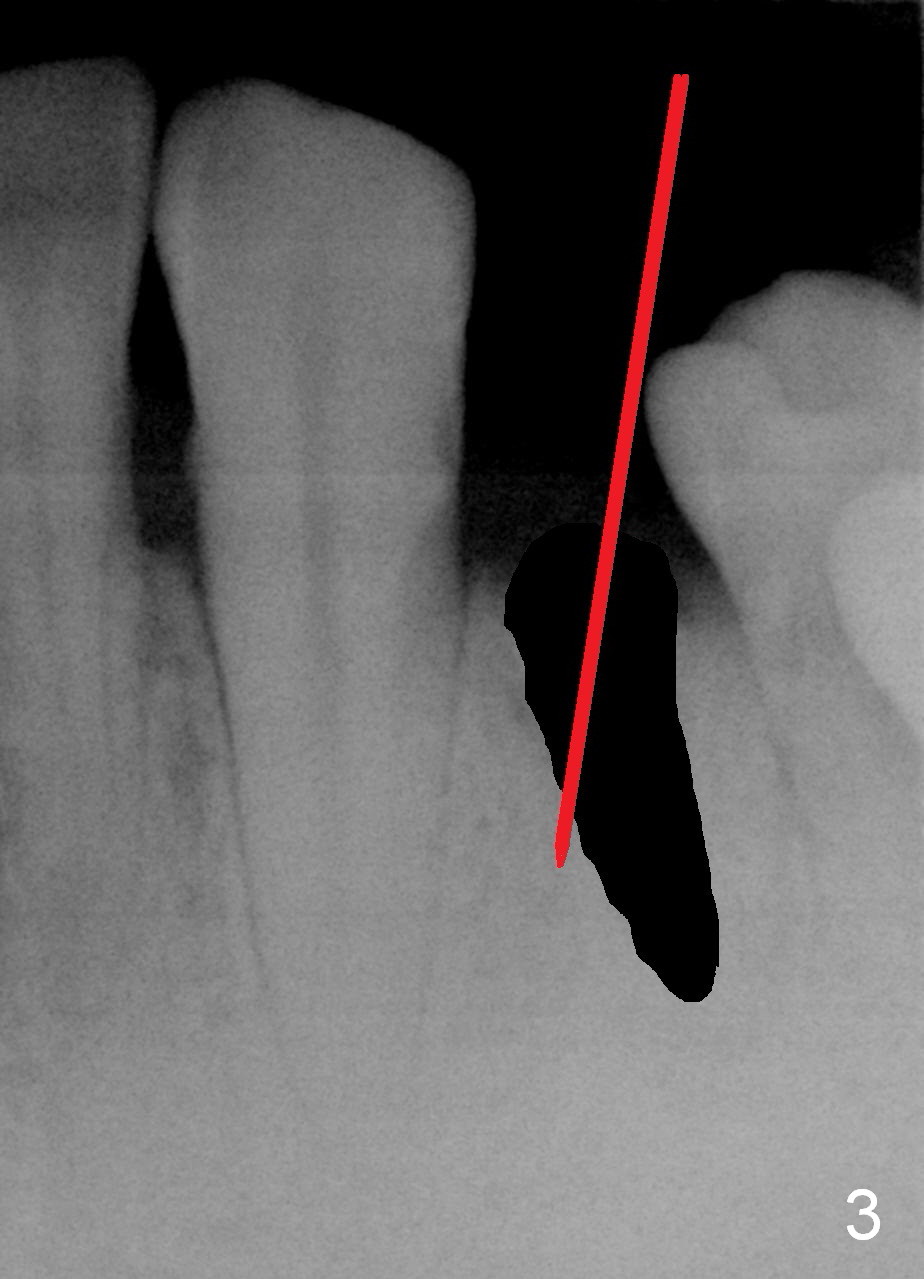

A 48-year-old man requests restoring the fractured tooth #21 (Fig.1). The socket seems to be oblique (Fig.2, no Antibiotic). Also considering the thin buccal plate, the initial osteotomy should be established in the mesiolingual slope (Fig.3). Change the trajectory once the entry is made (Fig.4) and take PA for confirmation. A 4x13 mm implant is to be placed (Fig.5). Why should the implant placed lingually? In fact the implant is placed too lingually. What is the reason?